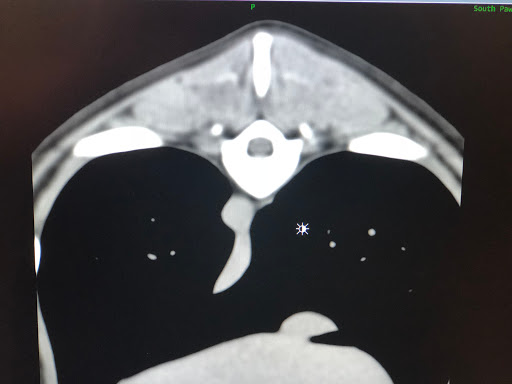

• South Paws Veterinary Surgical Specialists

South Paws Veterinary Surgical Specialists